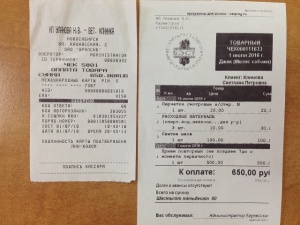

– салфетка стерильная марлевая 16 см х 14 см (33,95 руб.), салфетка стерильная марлевая 45 см х 29 см 4 шт. (155,20 руб.), бинт стерильный 7м х 14 см 7 шт. (169,75 руб.), хлоргексидина биглюконат раствор водный х 10 шт. (88,75 руб.) согласно листу назначений от 04.06.2016 (чек, товарный чек 2) - 447,65 руб.;

– салфетка стерильная марлевая 16 см х 14 см (33,95 руб.), салфетка стерильная марлевая 45 см х 29 см 4 шт. (155,20 руб.), бинт стерильный 7м х 14 см 7 шт. (169,75 руб.), хлоргексидина биглюконат раствор водный х 10 шт. (88,75 руб.) согласно листу назначений от 04.06.2016 (чек, товарный чек 2) - 447,65 руб.;

– оплата приема от 15.06.2016 и от 01.07.2016 хирург Козлов Евгений Матвеевич, клиника Бэст (чек 1, листы назначений – документ 1 и документ 2) – 650 руб.;

– оплата приема от 15.06.2016 и от 01.07.2016 хирург Козлов Евгений Матвеевич, клиника Бэст (чек 1, листы назначений – документ 1 и документ 2) – 650 руб.;